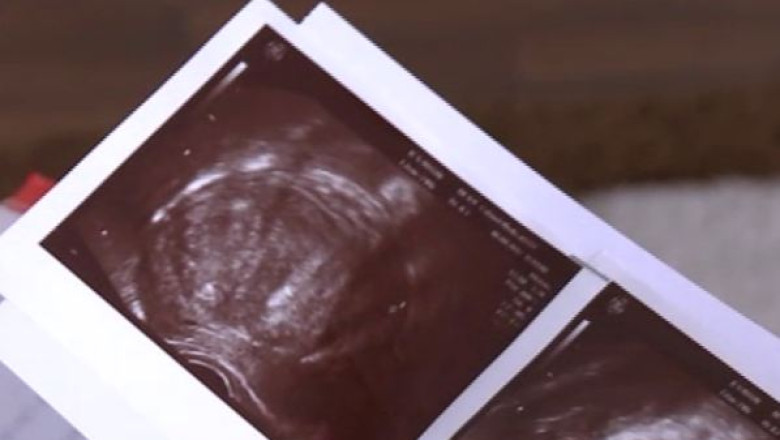

Sunt însă multe femei care ignoră aceste probleme şi ajung la medic când deja e prea târziu. Fibromul uterin este tumora cel mai des întâlnită la nivelul uterului şi apare în general la femeile aflate la vârsta fertilă din cauza dereglărilor hormonale. Una din trei femei din România are asemenea tumori.

„Fibrom mare este acela care depășește diametrele unei sarcini de 12 săptămâni sau în centimetri, cam 12 centimetri, care are indicații de intervenție chirurgicală”, declară Gheorghe Peltecu, managerul spitalului Filantropia.

Fibromul uterin poate provoca avorturi spontane, naşteri premature sau chiar infertilitate. Tratamentul se face însă individualizat, fie că este unul chirurgical sau medicamentos.